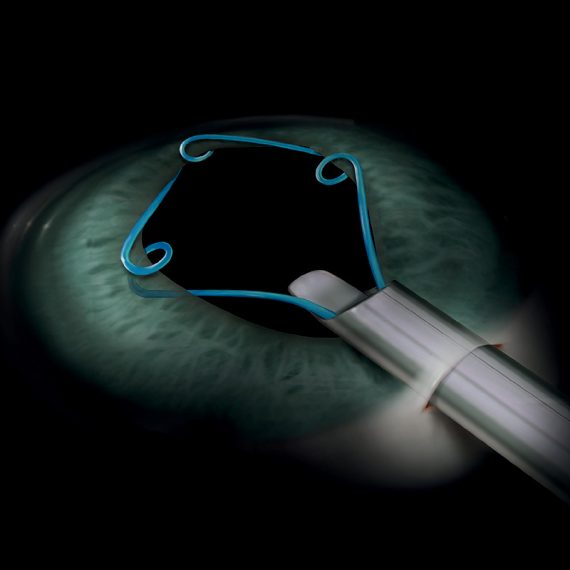

MST Malyugin Ring®Exclusive to IQ Medical, the MST Malyugin Ring® provides...Code: MAL-0001, MAL-0002, MAL-1001, MAL-1002Explore

MST Malyugin Ring®Exclusive to IQ Medical, the MST Malyugin Ring® provides...Code: MAL-0001, MAL-0002, MAL-1001, MAL-1002Explore -